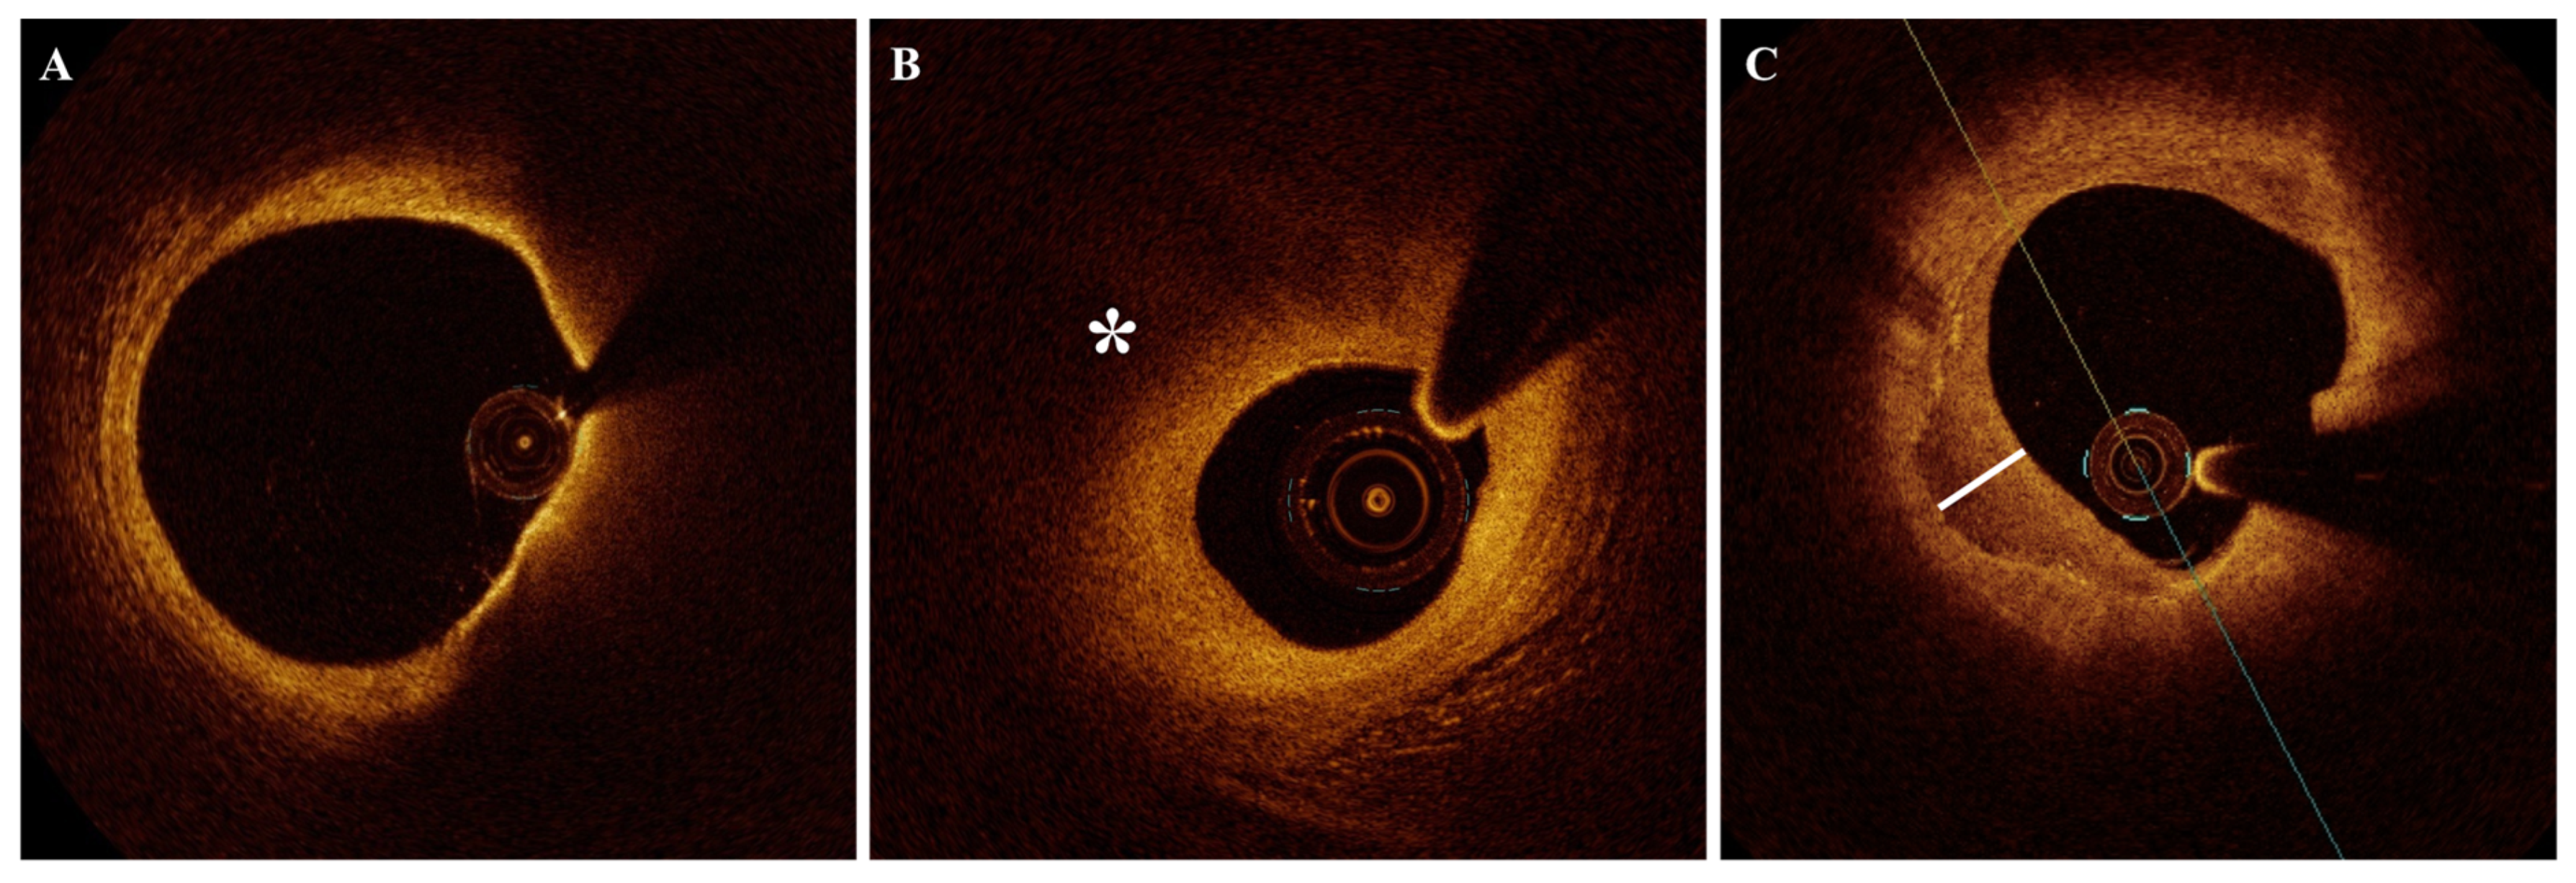

2.3. Healed Plaques

2.4. Macrophage Infiltration (MØI)

2.5. Cholesterol Crystals (CCs)